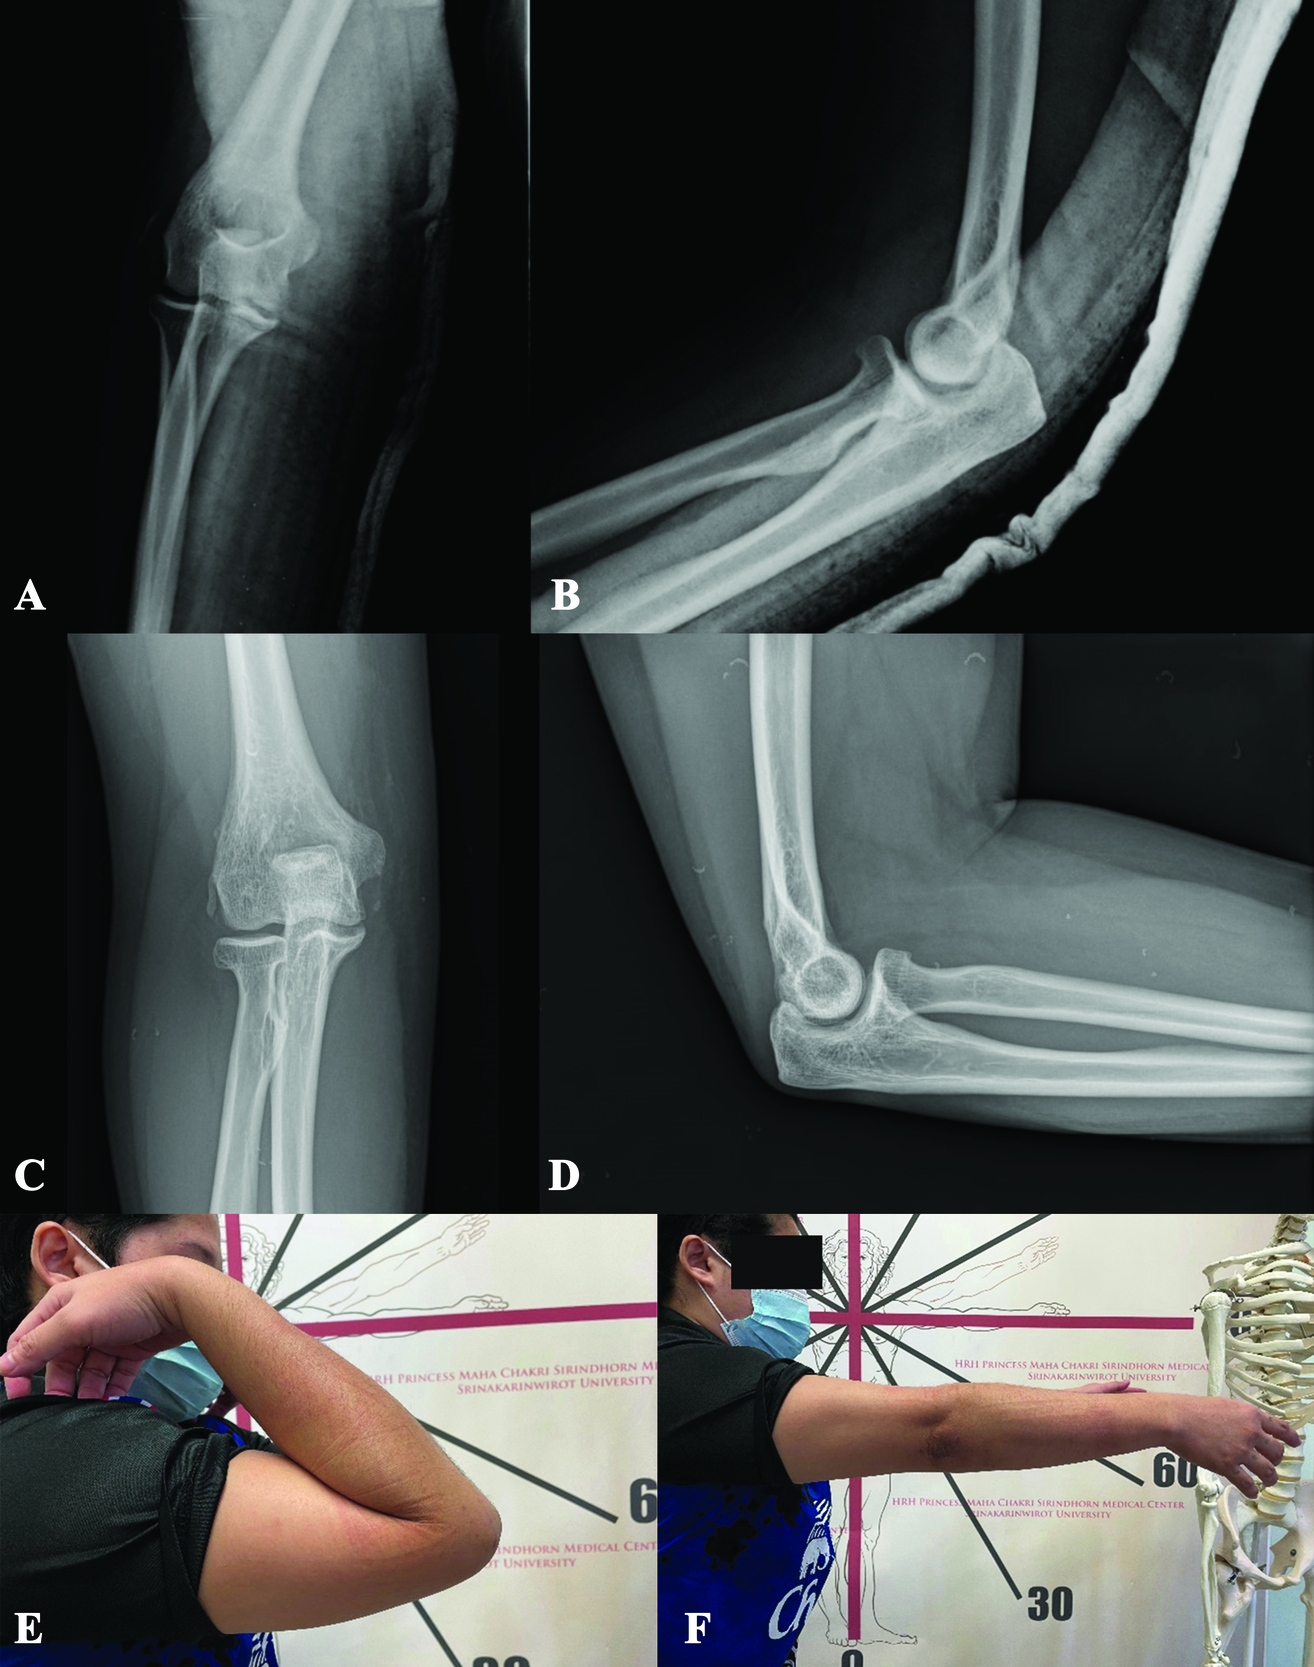

A subcutaneous tunnel was created from the previous incision toward the posterolateral portal. The sutures’ ends from the posterolateral portal were retrieved from the incision through this tunnel. Lastly, sutures were tied over the anconeus fascia to repair and imbricate the LCL (Fig.2F). After the repair, the drive-through sign and ulnohumeral opening gap were confirmed negative. Likewise, elbow stability was examined, and no subluxation resulted during end extension. The patient was immobilized with a long arm splint, and the elbow joint was congruent after the operation (Fig.3A-B).

At one month postoperative, she reported complete pain recovery with active elbow flexion of 120 degrees, extension of -10 degrees, and negative varus and valgus stress tests. Three months after surgery, her elbow gained full range of motion, 140 degrees flexion, and full extension, without any joint subluxation (Fig. 3C-F). In addition, the posterolateral drawer test and pivot shift apprehension test were negative at this follow-up. At the most recent follow-up, six months postoperative, a visual analog scale of 0, Quick DASH score of 29.5, and Mayo elbow performance index of 95 signify satisfactory functional outcomes.